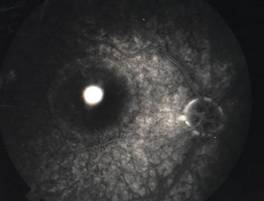

RETINITIS PIGMENTOSA |

Retinitis pigmentosa is the most common of a group of hereditary progressive retinal degenerations or dystrophies. There is considerable variation and overlap among the various forms of retinitis pigmentosa. Common to all of them is progressive degeneration of the retina, specifically of the light receptors, known as the rods and cones. The rods of the retina are involved earlier in the course of the disease, and cone deterioration occurs later. In this progressive degeneration of the retina, the peripheral vision slowly constricts and central vision is usually retained until late in the disease. Etiology

Ophthalmic features